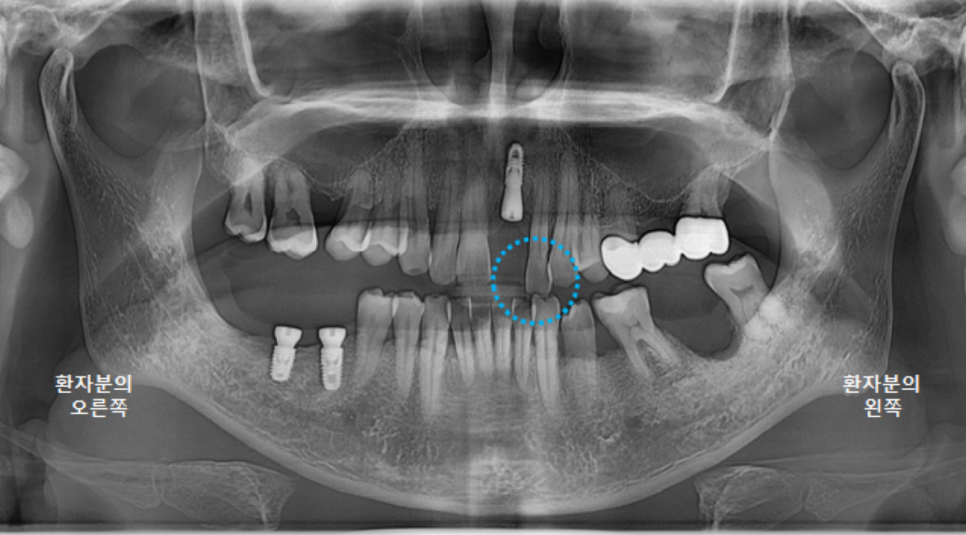

깨끗하게 뿌리조각과 염증을 제거하고 파노라마 엑스레이를 촬영했습니다.

(사진은 왼쪽어금니 발치와 오른쪽 어금니 수술 이후 촬영한 사진입니다^^)

뼈가 많이 녹아 있는 상태여서, 나중에 임플란트 식립시에 뼈이식이 꼭 필요할 것으로 보입니다.

보철물을 다 붙이고 나서 촬영한 파노라마 엑스레이입니다.

앞니가 들어가서 심미적으로도 좋아졌고,

교합 평면도 좋아졌습니다.

이제 환자분의 식사가 조금 더 편해져서, 잘 드실 수 있게 되었습니다. ^^